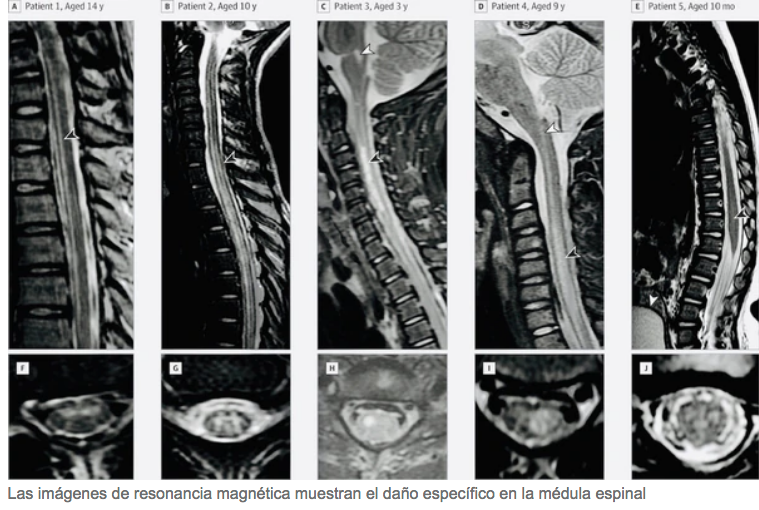

AFP I Desconcertados por el aumento repentino de niños con parálisis de brazos o piernas en Estados Unidos, los funcionarios de salud dijeron el martes que están investigando si un virus o un trastorno autoinmune pueden ser las causas.

Un total de 252 casos del trastorno conocido como mielitis flácida aguda (MFA) se están investigando en todo el país, con un aumento de 33 desde la semana pasada, dijo Nancy Messonnier, directora del Centro Nacional de Inmunización y Enfermedades Respiratorias del Centro de Control y Prevención de Enfermedades (CDC).

La mayoría de los casos se presentan en niños de entre dos y ocho años. Casi todos presentaron fiebre y enfermedades respiratorias de tres a diez días antes de experimentar repentinamente parálisis en sus brazos o piernas.

El centro ha analizado 125 muestras de líquido de la médula espinal y la mitad de ellas dieron positivo para rinovirus o enterovirus, que comúnmente produce síntomas como fiebre, secreción nasal, vómitos, diarrea y dolores corporales.

Sin embargo, los científicos todavía están desconcertados sobre la causa precisa de la parálisis repentina, ya que estos virus son comunes, pero el MFA no lo es.